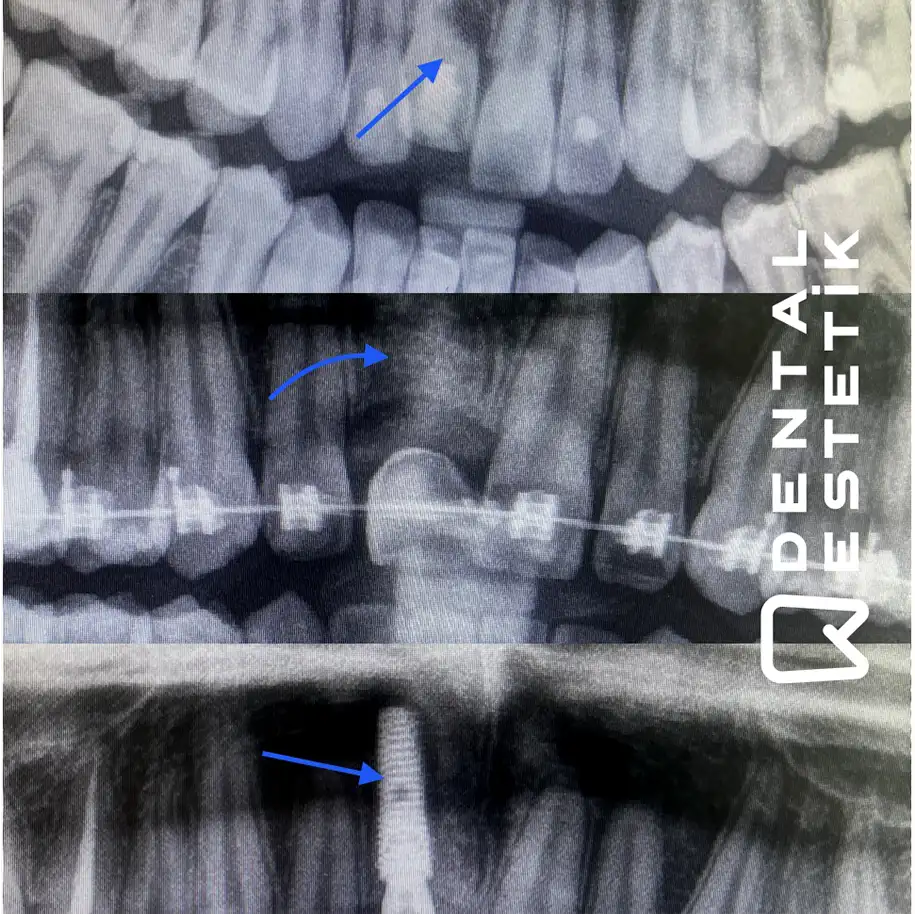

ZAHNMEDIZIN VORHER NACHHER